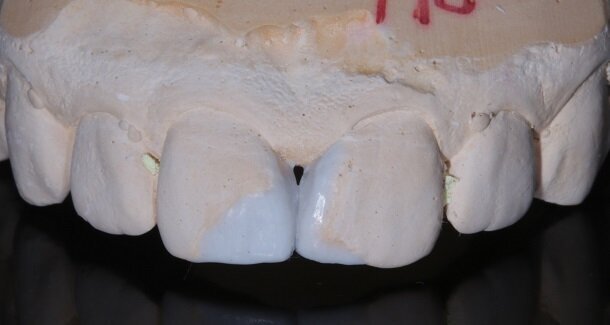

The figures show the clinical work flow involved. In the 1st appointment Oral prophylaxis, oral hygiene instructions were followed by an impression that was sent to the lab for a wax up [Fig 3 and 4]. In the subsequent appointments, Endodontic treatment was followed by Intra and extra coronal office bleaching using the Pola office bleaching kit. After two weeks, the shade stabilised post bleaching. Shade selection, rubber dam isolation and preparation was done on both the teeth to receive Direct composite veneers so as to close the midline diastema as well as correct the fractured teeth and the slight mal-alignment. Controlled Body Thickness (CBT) technique of layering was used with 3M Z350XT shades - Dentin shades A3, A2 and Enamel shades A2, clear translucent [Figures 5 to 11]. This was followed by the Finishing and polishing protocol as described in the figures.

Characterisation begins during Dentin Layering itself. [Fig 9] Shape of the tooth is extremely important. A well-made putty key from a wax-up or a mock-up can help in maintaining shape of the tooth. [Fig 3 and 4]